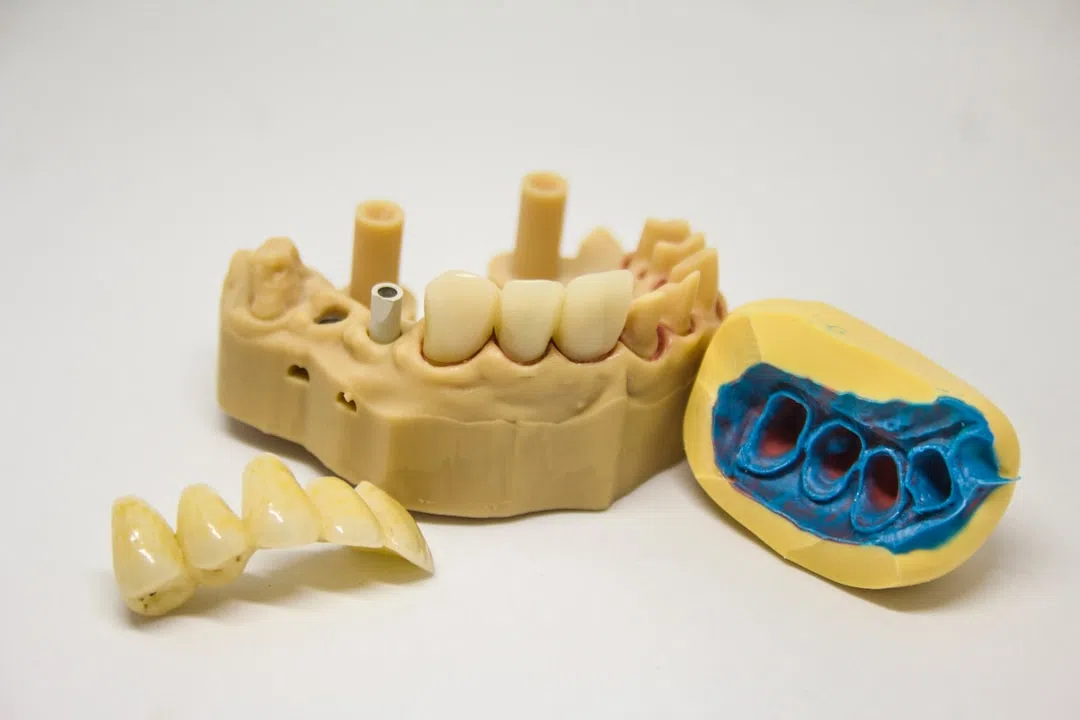

이 영상은 ‘임플란트 후 관리법’이라는 주제로 많은 분들이 참고할 만한 유용한 정보를 담고 있습니다. 영상을 보며 제가 체험했던 여러 방법들이 실제로 어떻게 적용되는지 생생하게 확인할 수 있으니, 여러분께도 큰 도움이 될 것이라 믿습니다.